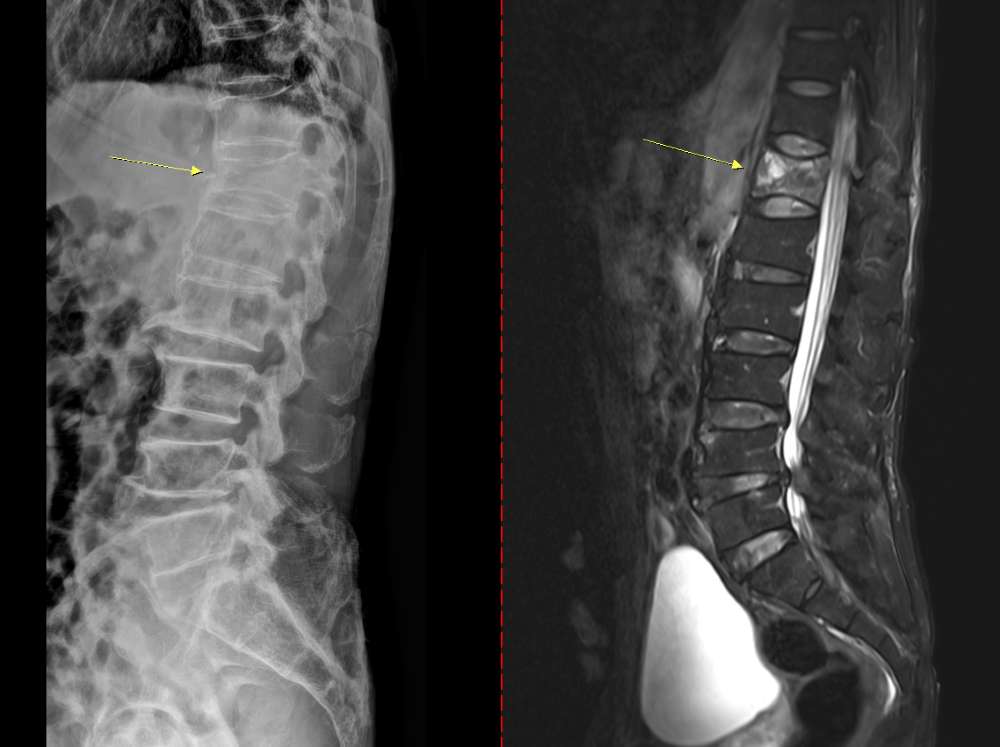

¡ã °ñ´Ù°øÁõ¼º ¾Ð¹Ú°ñÀý ȯÀÚÀÇ Ã´Ãß x-ray(¿ÞÂÊ)¿Í MRI(¿À¸¥ÂÊ)

°ñ´Ù°øÁõÀº Ãʱâ ¡Èİ¡ ¶Ñ·ÇÇÏÁö ¾Ê¾Æ ƯÈ÷ ÁÖÀÇÇØ¾ß ÇÑ´Ù. ÅëÁõÀ̳ª ÀÚ°¢ Áõ»óÀÌ °ÅÀÇ ¾ø´Ù°¡ ½Ã°£ÀÌ Áö³ª °¡º­¿î Ãæ°Ý¸¸À¸·Îµµ ¼Õ¸ñÀ̳ª ´ëÅð°ñ(¾ûµ¢ÀÌ»À)ÀÌ °ñÀýµÇ¸é¼­ µÚ´Ê°Ô Áø´ÜµÇ´Â °æ¿ìµµ ÀÖ´Ù. ¶§·Î´Â µîÀÌ ±Á°Å³ª ۰¡ ÁÙ¾îµå´Â ôÃß ¾Ð¹Ú°ñÀýÀÌ ³ªÅ¸³¯ ¼öµµ ÀÖ´Ù. Ä¡·á ¾øÀÌ ¹æÄ¡ÇÏ¸é »À´Â Á¡Á¡ ¾àÇØÁö°í ôÃß¿Í ¼Õ¸ñ, ´ëÅð°ñ °ñÀý µî Áß´ëÇÑ °ñÀýÀÌ ¹ß»ýÇÒ ¼ö ÀÖ´Ù.